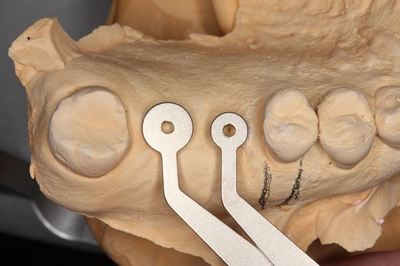

EZ STENT イージーステントを用います。

熱可塑性樹脂ですので、熱湯で温めることで透明になり成型できます。

スリーブを追加しています。

模型に圧接してステントの完成です。